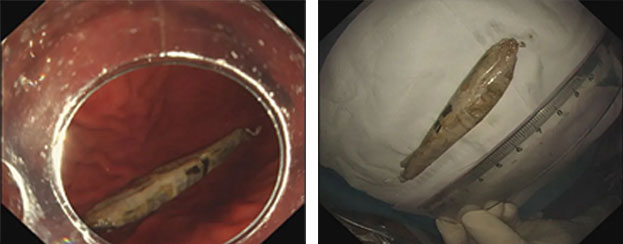

患者服藥時,一個不留神,將帶有硬錫箔包裝的藥品直接吞下。誤吞的帶錫箔殼藥片邊緣尖銳,患者感咽喉部疼痛伴異物感。脾胃病科(消化內(nèi)科)行急診胃鏡異物取出術(shù)。電子胃鏡進入食管,發(fā)現(xiàn)藥品正好卡在食管入口處,食管粘膜有多處充血糜爛灶,在異物鉗等器械輔助下,成功將異物安全取出。患者術(shù)后未發(fā)生食管新的損傷,無食管穿孔等并發(fā)癥,恢復良好。

內(nèi)鏡下取異物